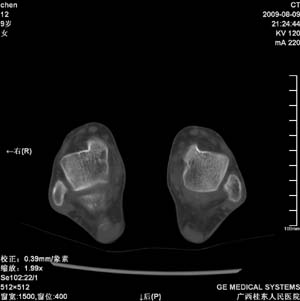

标题: PED2867:右侧内踝肿胀,骨质改变,请各位老师会诊 [打印本页]

标题: PED2867:右侧内踝肿胀,骨质改变,请各位老师会诊

九岁小朋友,近期左侧内踝疼痛,局部肿胀,平时无特殊,近期经常溜干冰

对不起,是右侧内踝肿胀

双踝关节骨质及发育未见异常。

左侧内踝密度增高,请结合临床!